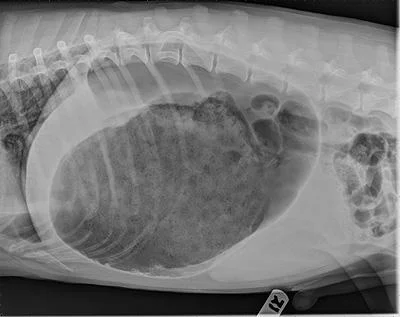

Note the distended abdomen in this bloated dog

Radiographic appearance of GDV: The pylorus is positioned dorsal to the body of the stomach in this x-ray, indicating the stomach has been twisted.

The diagnosis is made by physical exam and confirmed by x-rays. It is possible to have a bloated stomach that is not twisted, as well as a distended abdomen from other reasons that would not necessitate surgical intervention, thus it is important to confirm the diagnosis with imaging. Once the diagnosis is established, emergency treatment can begin.